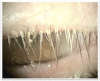

Demodex blepharitis is a common disease of the eyelid, affecting approximately 25 million Americans. This article reviews what is known about the mechanisms and impact of Demodex blepharitis, risk factors, signs and symptoms, diagnostic techniques, current management options, and emerging treatments. Demodex mites contribute to blepharitis in several ways: direct mechanical damage, as a vector for bacteria, and by inducing hypersensitivity and inflammation. Risk factors for Demodex blepharitis include increasing age, rosacea, and diabetes. The costs, symptom burden, and psychosocial effects of Demodex blepharitis are considerable. The presence of collarettes is pathognomonic for Demodex blepharitis. Redness, dryness, discomfort, foreign body sensation, lash anomalies, and itching are also hallmarks of the disease. Although a number of oral, topical, eyelid hygiene and device-based options have been used clinically and evaluated in studies for the management of Demodex blepharitis, none have been FDA approved to treat the disease. Recent randomized controlled clinical trials suggest that lotilaner ophthalmic solution, 0.25%, is a topical treatment with the potential to eradicate Demodex mites and eliminate collarettes and eyelid redness for an extended period.